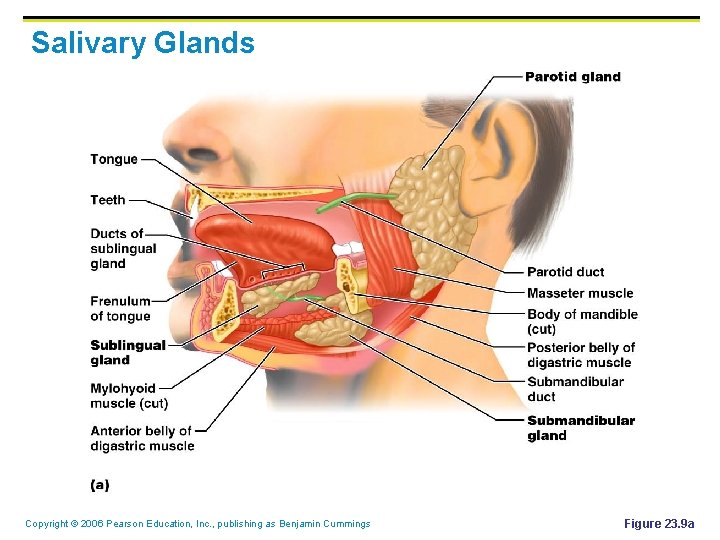

Salivary Glands Copyright © 2006 Pearson Education, Inc. , publishing as Benjamin Cummings Figure 23. 9 a

Salivary Glands § Produce and secrete saliva that: 1. Cleanses the mouth 2. Moistens and dissolves food chemicals 3. Aids in bolus formation 4. Contains digestive enzymes that break down starch (sugar) Copyright © 2006 Pearson Education, Inc. , publishing as Benjamin Cummings

Digestive Processes in the Mouth § Food is ingested § Mechanical digestion begins (chewing) § Propulsion is initiated by swallowing § The pharynx and esophagus serve as conduits to pass food from the mouth to the stomach Copyright © 2006 Pearson Education, Inc. , publishing as Benjamin Cummings